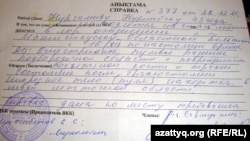

Нұрлыбек Нұрғалиев сол күні қалалық ауруханаға түскен. Бірақ, оның әйелі Гүлжамал Нұрғалиеваның айтуынша, Жаңаөзенде дәрігерлер жетіспегендіктен сегіз сағаттан кейін Нұрлыбек Нұрғалиевті Ақтау қаласындағы ауруханаға апарған.

– Ақтау ауруханасында өңешіме дереу операция жасалғанымен оқты денемнен ала алмады, қашып кетті дейді. Түтік арқылы дем алып 10 күн жаттым, сөйлей алмаймын. Бірақ ойламаған жерден ауруханадан шығарып жіберді. «Оқты Жаңаөзенде алады» деп айтты. Ал жаңаөзендік дәрігерлер оқты алуға болмайды деп отыр, – дейді Нұрлыбек.

Оның айтуынша, дәрігерлер оны Ақтау ауруханасынан қаңтардың 5-інде шығарған.